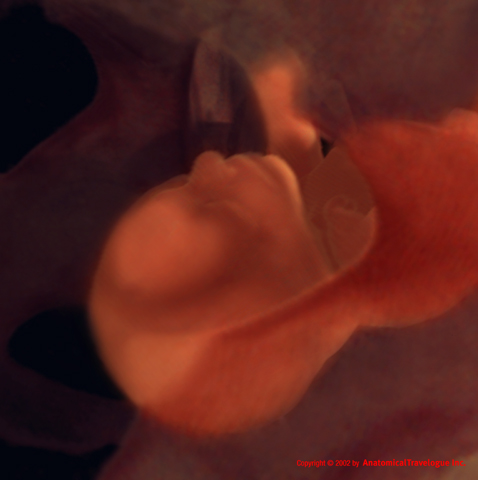

Con più di 45 cm di lunghezza il vostro bambino sta crescendo bene. Sta imparando cosa si prova a respirare, inalando ed esalando fluido amniotico per perfezionare la sua abilità. E’ in grado anche di succhiarsi il pollice, girare la testa, ingoiare, battere gli occhi e afferrare.

La trentasettesima settimana di gravidanza